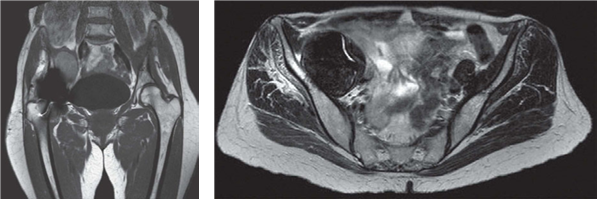

Figures 2.5a and 2.5b MRI of right MOM hip resurfacing implant demonstrating ALVAL mass.

I would also order an MRI scan with metal artifact reduction sequences (MARS). This is operator dependent but can give clear images of fluid collections or solid lesions (pseudotumours) around the hip. EXAMINER : This is the MRI scan obtained. What does it show?

(Figure 2.5.) CANDIDATE : The MRI is a T2-weighted image coronal view, which demonstrates an intra-pelvic mass. EXAMINER : This was a pseudotumour. In fact the mass could be felt clinically when examining the abdomen. EXAMINER : What are you going to do? CANDIDATE : This patient requires urgent revision surgery to the hip. EXAMINER : She is very scared of surgery and would prefer to avoid it. CANDIDATE : I would stress the important of early revision surgery as the longer the MOM resurfacing implant is left in place the more extensive the soft tissue destruction will most likely be. EXAMINER : What are the principles of surgery for pseudotumours? CANDIDATE : The pseudotumour needs to be managed with aggressive debridement of all involved soft tissue. It is important to do a thorough debridement of the abnormal tissue similar to the treatment of infection. The surgery should be preformed by an experienced hip surgeon.